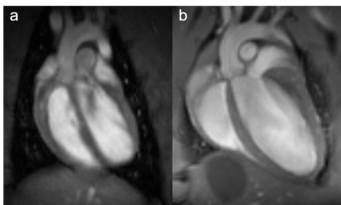

Fig. 1: Rat and mouse heart MRI. 4-chamber-views of a rat (a), upper panel and mouse heart (b), lower panel are displayed. Beside the lumen of the left and right chamber, the left and right atria, the myocardium and the up-going vessels are visible. For rat a 72 mm volume transmit-only together with 20 mm recieve-only planar surface coil, both room temperature, and for mouse the 72 mm volume transmit-only and the cryogenic 4 element 1H array receive-only coil were used. Intragate Flash (Fast Low Angle Shot) sequence for rat (repetition time: 6.2 ms; echo time: 1.3 ms; oversampling:150; flip angle: 10 deg; slice thickness: 1.0 mm; FOV: 45x45 mm and matrix: 128x128 .Intragate UTE (Ultra Short Echo Time) for mouse: repetition time: 8.0 ms; echo time: 0.36 ms; oversampling: 100; flip angle: 15 deg; slice thickness: 1.0 mm; FOV: 22x22 mm and matrix: 128x128.

MRI is a well-established modality for imaging of the cardiovascular system in rat and mice. Beside determination of tissue, organ or tumor sizes, our main focus lies on monitoring changes over time after treatment of transgenic mice. One of the best-known forms of dynamic MRI experiments is the functional MRI, typically monitoring changes in blood flow. In the recent years MRI has become the standard for the quantitative evaluation of cardiac function, masses, and infarct size. Wall motion and strain analysis are used to display myocardial dysfunction. To obtain information on the morphology and functional parameters of rat and transgenic mice heart, we established standard protocols that enable us to rapidly acquire high quality images.